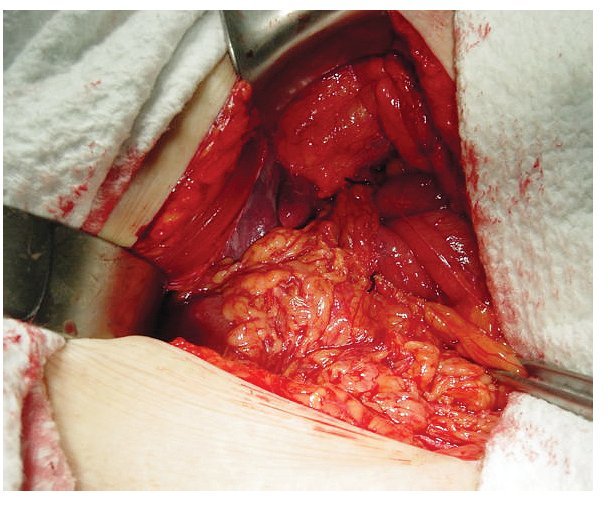

Se trata de paciente femenino de 75 años de edad, la cual acude al servicio de urgencias por presencia de vómitos en varias ocasiones de contenido gástrico, intolerancia a los alimentos, malestar generalizado y datos francos de deshidratación secundaria, con 15 días de evolución desde el inicio de su padecimiento. La paciente tiene antecedentes de diabetes mellitus, hipertensión arterial y refiere gastritis crónica en tratamiento. A su ingreso se encuentra orientada, conciente y sin datos de alarma abdominal, por lo que es internada para su estudio y estabilización con sospecha de cuadro de estenosis péptica pilórica. Se coloca sonda nasogástrica drenando aproximadamente 3 L de material gástrico espeso y restos de alimentos. Laboratorios a su ingreso con hemoglobina de 10 mg/dL, leucocitosis de 13,000 mm3, glucosa 96 mg/dL, urea 30 mg/dL, creatinina 1.8 mg/ dL. Una vez con la paciente en mejores condiciones, se decide realizar panendoscopia encontrando un cálculo biliar gigante impactado en el bulbo duodenal (Imágenes 1 y 2) realizándose múltiples maniobras de extracción con pinzas de cuerpo extraño, las cuales no fueron exitosas. Se realizó ultrasonido demostrando la presencia del cálculo impactado en duodeno, no se apreció dilatación de vías biliares (Imagen 3). Con estos hallazgos se decide someter a la paciente a cirugía, encontrando la presencia de un cálculo biliar gigante dentro del bulbo duodenal con vesícula biliar escleroatrófica, se realiza duodenotomía y extracción del cálculo con duodenorrafia en 2 planos tipo Heineken-Mikulicz sin incidentes transoperatorios (Imágenes 4, 5 y 6) y con adecuada evolución, siendo egresada al octavo día del posoperatorio.

Imagen 2. Cálculo biliar impactado en duodeno.